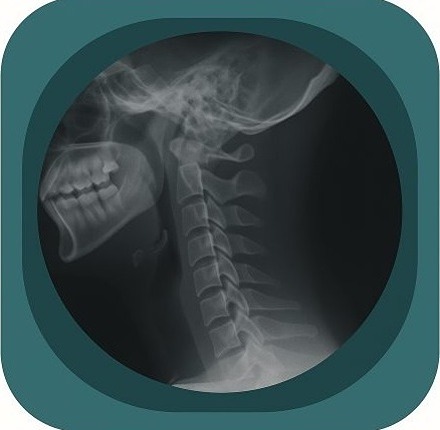

Explore high-quality X-ray anatomy from head to toe. Our database features carefully labelled images to visualize fine structuresโ€”perfect for radiologists, students, and surgeons.